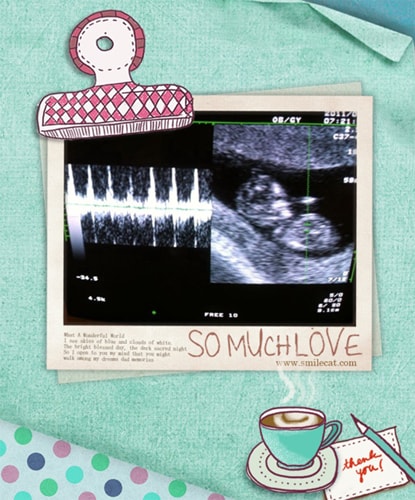

噗通!噗通!噗通!那強而有力的心跳聲,是世界上最美好的聲音。 懷孕將近16週,早就該公布這個喜訊了, 不過自從懷孕後,身體陸陸續續出現了許多狀況, 導致我根本無心好好經營部落格, 今天總算比較舒服一點了, 所以趕緊整理了照片,跟大家分享這個喜訊。 ♥100.01.28 我的肚子有了生命 唉唷!要放上這個驗…